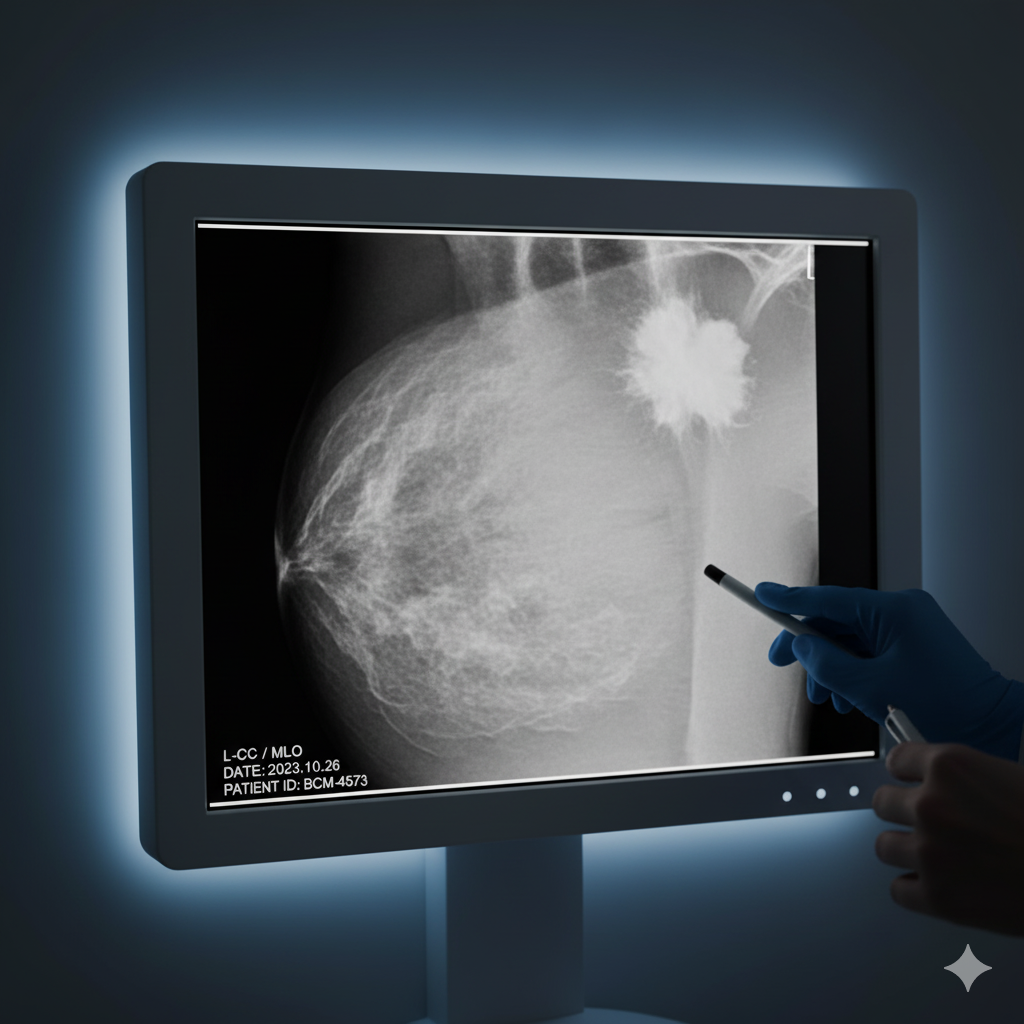

Esta nueva técnica permite analizar las modificaciones epigenéticas del ADN, como la metilación, que pueden influir en la expresión de genes sin alterar la secuencia genética. Al comprender cómo estas modificaciones afectan a las células tumorales, los investigadores pueden identificar patrones que predicen la evolución del cáncer y su respuesta a los tratamientos.

En el contexto de la investigación sobre el cáncer, estas herramientas epigenéticas ofrecen un enfoque más preciso y personalizado para el diagnóstico y tratamiento. Al identificar las alteraciones epigenéticas específicas de cada paciente, es posible adaptar las terapias de manera más efectiva, mejorando así los resultados y reduciendo efectos secundarios.

Además, este enfoque permite detectar cambios en las células tumorales en etapas tempranas, lo que facilita la intervención precoz y mejora las tasas de supervivencia.